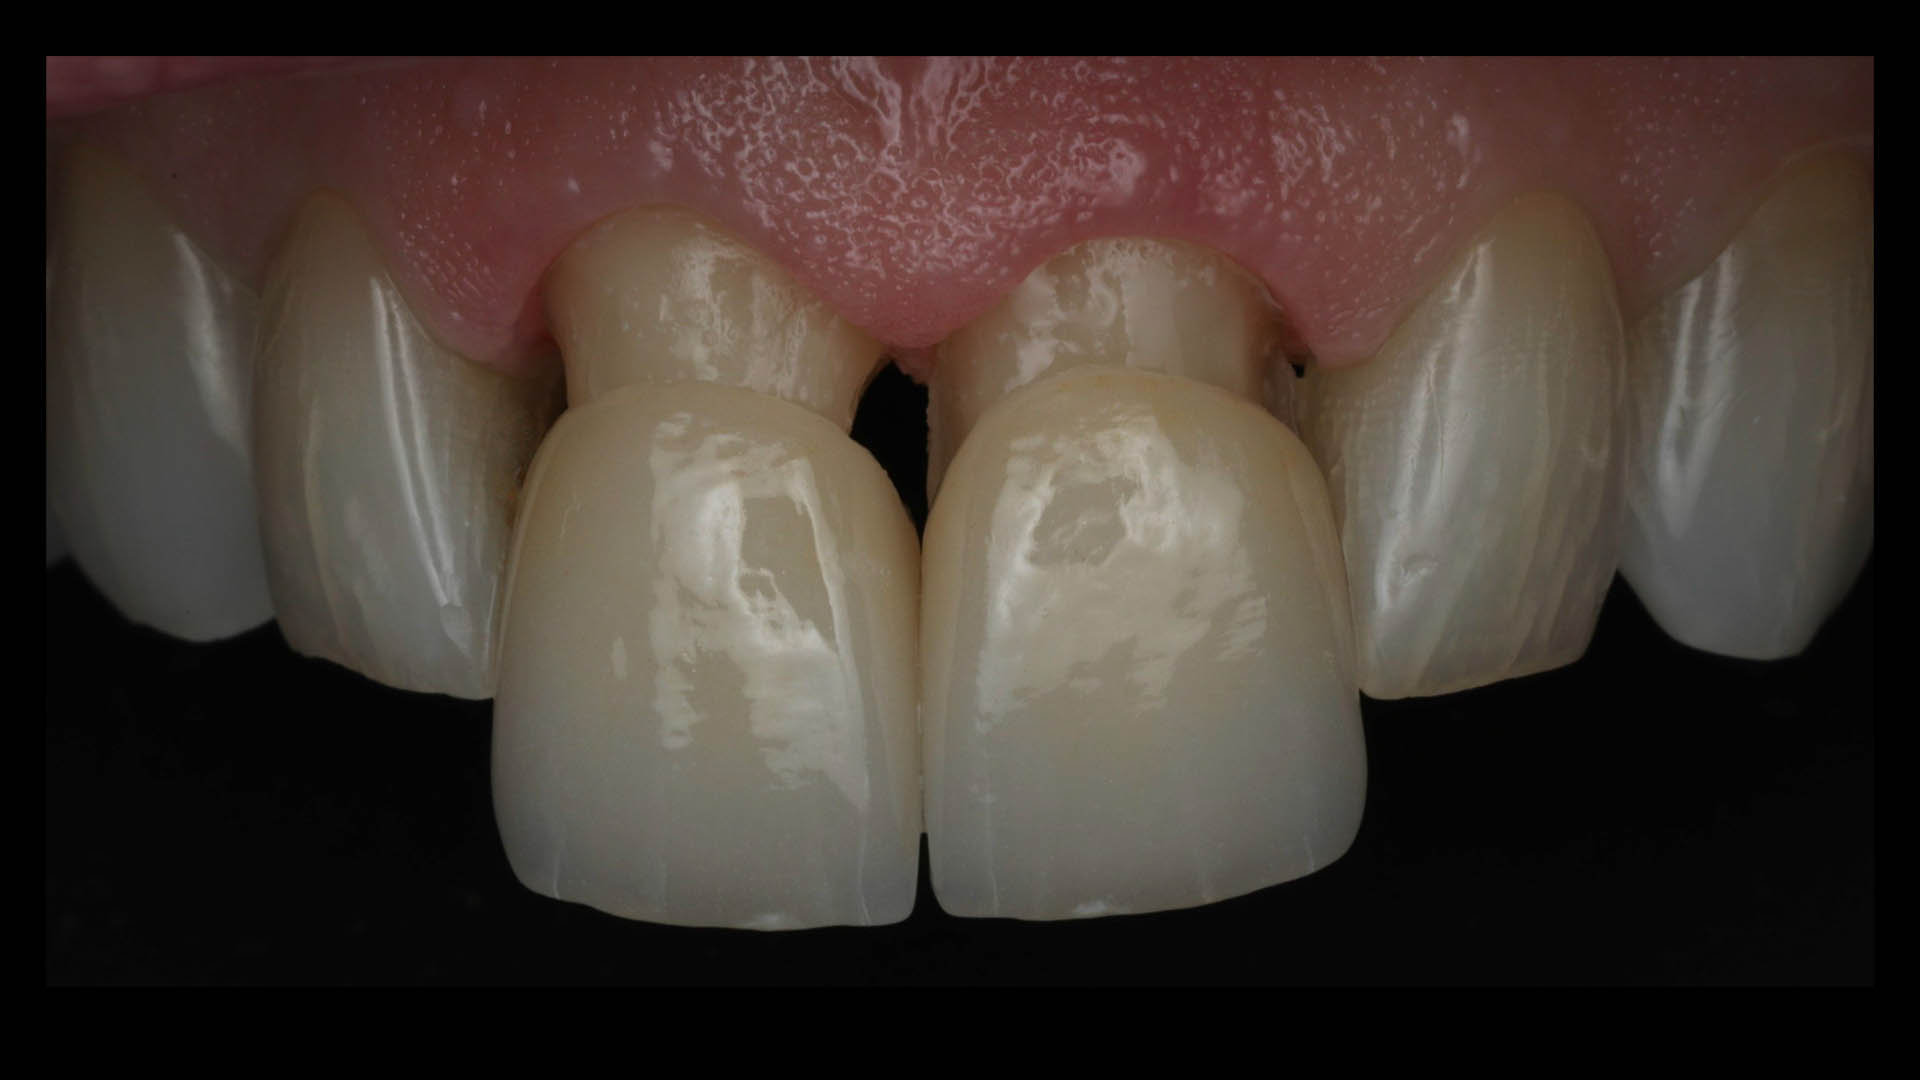

Take a glimpse into the magic of Coral Gables Dentistry through our before and after pictures. See firsthand the incredible smile makeover transformations that have brought confidence and joy to our patients.